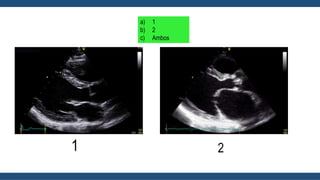

Ecocardiograma

• Permite el Dx de Estenosis Mitral

• Evalúa la severidad (Gradientes, Orificio valvular, Presión en arteria

pulmonar).

• Ayuda al Dx de lesiones Valvulares acompañantes.

• Valora el Tamaño, condiciones y función del VD (Afectado por aumento

de presiones pulmonares).

Guadalajara, J. F. (2012). Cardiología. CDMX: Mendez Editores.

a) 1

b) 2

c) Ambos

1 2

Eje Corto

El área de la válvula mitral se mide

mediante planimetría directa de eje corto.

Ecocardiograma • Permite elDx de Estenosis Mitral • Evalúa la severidad (Gradientes, Orificio valvular, Presión en arteria pulmonar). • Ayuda al Dx de lesiones Valvulares acompañantes. • Valora el Tamaño, condiciones y función del VD (Afectado por aumento de presiones pulmonares). Guadalajara, J. F. (2012). Cardiología. CDMX: Mendez Editores.

a) 1 b) 2 c)Ambos 1 2